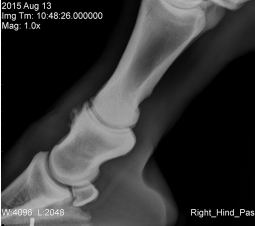

Du foretager halthedsudredning af en 12 år gammel hest. Efter diagnostiske blokader finder du disse røntgenforandringer. Hvilken kombination af blokader kunne MEST SPECIFIKT lokalisere hestens halthed?

1 Ramusanalgesi og abaxial sesamoid analgesi

2 Hovledsanalgesi og kodeledsanalgesi

3 Ramusanalgesi og lav 6-punkts analgesi (ringblok over koden)

4 Hovledsanalgesi og lav 6-punkts analgesi (ringblok over koden)

Det rigtige svar er 1